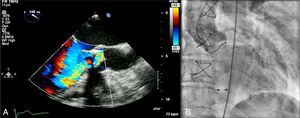

The postprocedural period was uneventful, with no vascular access complications, contrast-induced nephropathy or elevation of myocardial necrosis markers; there were also no arrhythmic complications such as high-degree atrioventricular block (the greater stiffness of the prosthetic ring and implantation in a higher position presumably protected the underlying conduction tissue). Clinically, the patient showed significant improvement in functional capacity and was discharged on the sixth day. The discharge transthoracic echocardiogram confirmed appropriate position and function of the CoreValve and no residual regurgitation (Figure 4). After 14 months of follow-up, the patient remains in NYHA class I and the prosthesis is functioning normally, with no regurgitation (Figure 5).